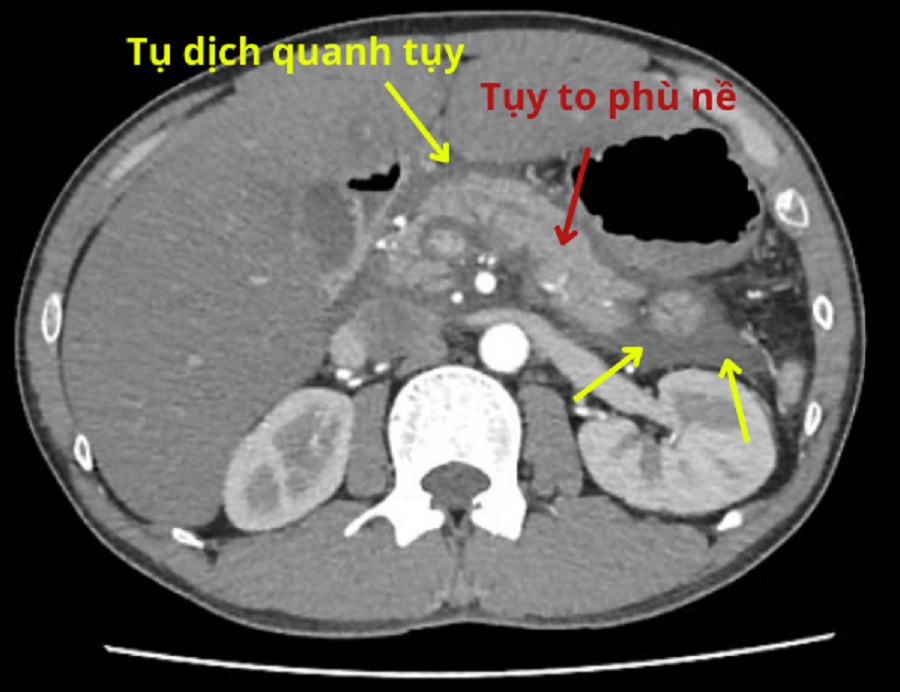

| Hình ảnh MSCT 160 lát cắt cho thấy bệnh nhân bị viêm tụy cấp đe dọa tính mạng |